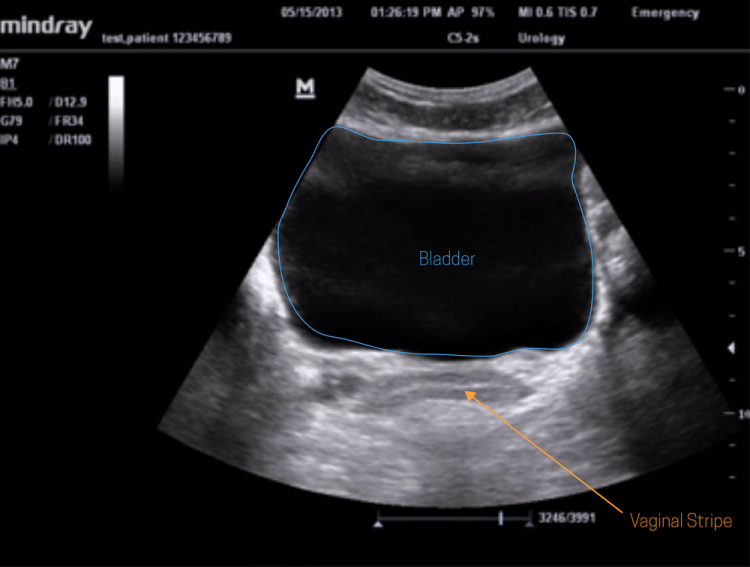

La ecografía común, también conocida como ultrasonido general, se utiliza para examinar diversas áreas del cuerpo. Es una técnica versátil que puede evaluar órganos del abdomen, pelvis, tiroides, vasos sanguíneos e incluso tejidos blandos. Por ejemplo, es comúnmente utilizada durante el embarazo para monitorear el desarrollo del feto o para detectar anomalías en órganos abdominales. Su capacidad para adaptarse a distintas necesidades la convierte en una herramienta diagnóstica ampliamente utilizada.